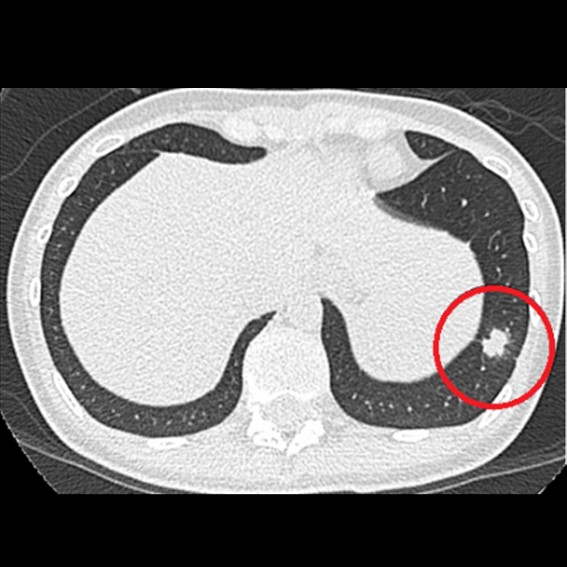

運用高科技尖端影像設備,提供貴賓精準的檢查、判讀、即時醫療、後續追蹤、健康管理或醫學中心轉介服務;從健檢診斷到後端治療,一條龍式服務。永越自成立以來,已服務超過16萬人次,每年通報件數超過千件,揪出包括:甲狀腺癌、肝腫瘤、肺癌、乳癌、子宮頸癌等重大異常的健康警訊,把握住早發現早治療的黃金關鍵。